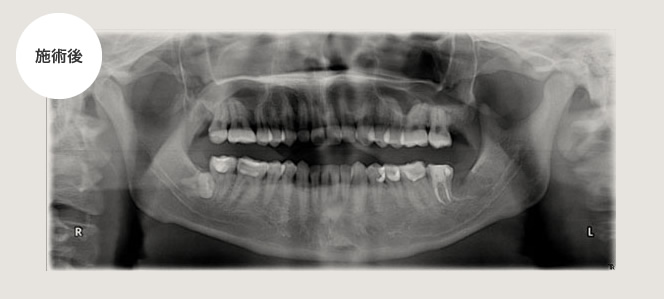

手前の歯が虫歯になってしまった例、及び抜く必要がない場合

左下がズキズキ痛むという主訴で来院されました。

原因は親知らずの一つ手前の歯が歯髄炎になってしまっていたので、神経の処置を通法通り行いましたが、親知らずの頭が一部でていたため、そこに汚れがたまり手前の歯が虫歯になってしまったため左下は抜歯しました。

右下は完全に骨の中に埋まっている状態でしたので抜く必要はありません。